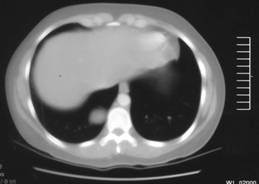

Figure-1:

CT scan with intravenous contrast revealed a 3.8 x 2.7 cm right paraspinal mass at the level of T10.